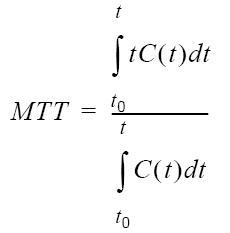

| MTT |  |  |

Mean Transit Time

Mean Transit Time (MTT) measures the length of time a certain volume of blood spends in the cerebral capillary circulation.